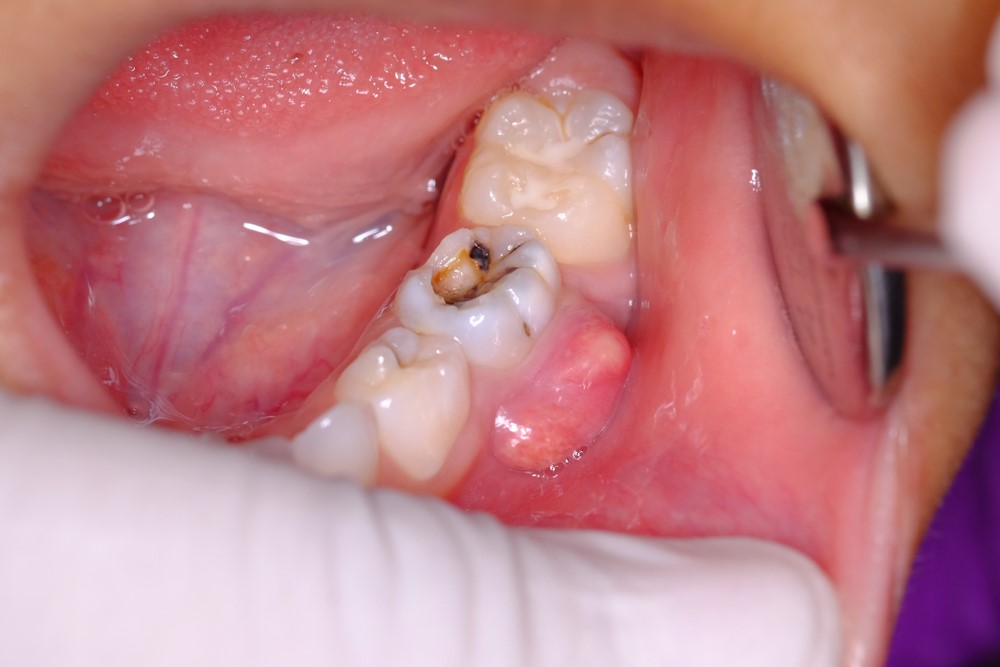

Sâu răng là nguyên nhân phổ biến dẫn đến viêm tủy. Khi lỗ sâu tiến sâu vào lớp ngà răng và không được trám lại, vi khuẩn sẽ dễ dàng tấn công vào tủy, gây viêm và hình thành ổ mủ.

(Sâu răng lâu ngày ở trẻ em hoặc người trưởng thành nếu không điều trị sẽ dẫn đến viêm tủy)(**)